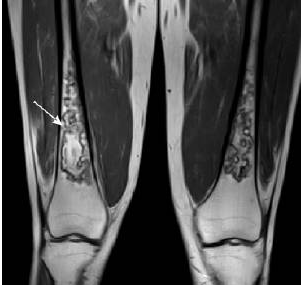

(1)病变好发于股骨下段及胫骨上段,双侧发病;

(2)病灶中心呈短T1脂肪信号,信号均匀或不均匀。

(3)病灶边缘呈迂曲的长T1信号带。T2WI分为2层,内层呈高信号带,反映充血水肿和肉芽组织;外层为低信号硬化带。

(4)病灶呈多发,形态不规则,并有融合趋势,呈典型“地图”样。

双边征,内缘高信号,外缘低信号,地图样改变